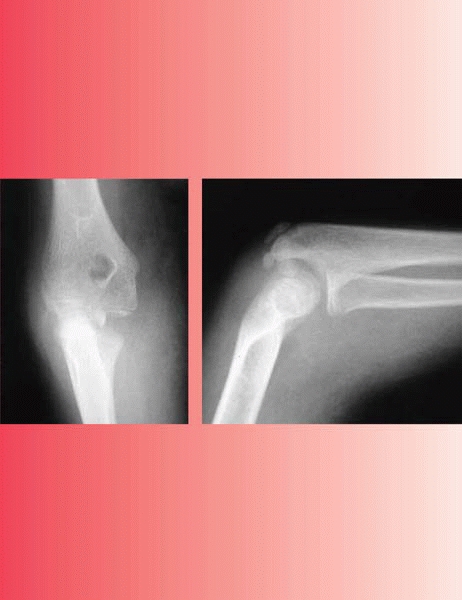

▪ FIGURE 6-1 A: AP view of a lateral condyle fracture demonstrating less than 2 mm displacement. B: Lateral view of a lateral condyle fracture demonstrating less than 2 mm of displacement. C:

Oblique view, looking at the lateral side of the elbow tangentially, showing greater than 2 mm of displacement. Without this radiograph, one may have assumed there was less than 2 mm of displacement, and treated the fracture nonoperatively. |

use in determining treatment or predicting outcome. If the amount of

maximum fracture displacement in all radiographs is ≤2 mm, then

nonoperative treatment with immobilization is indicated. Remember that

the AP and lateral views may underestimate the extent of fracture

displacement, so an oblique view is necessary (Fig. 6-1) when considering

nonoperative treatment. A prospective investigation of 112 lateral

condyle fractures with ≤2mm of displacement treated with splinting

reported that if the fracture line cannot be followed to the epiphysis,

the fracture is stable and not at risk for displacement1 (Fig. 6-2).